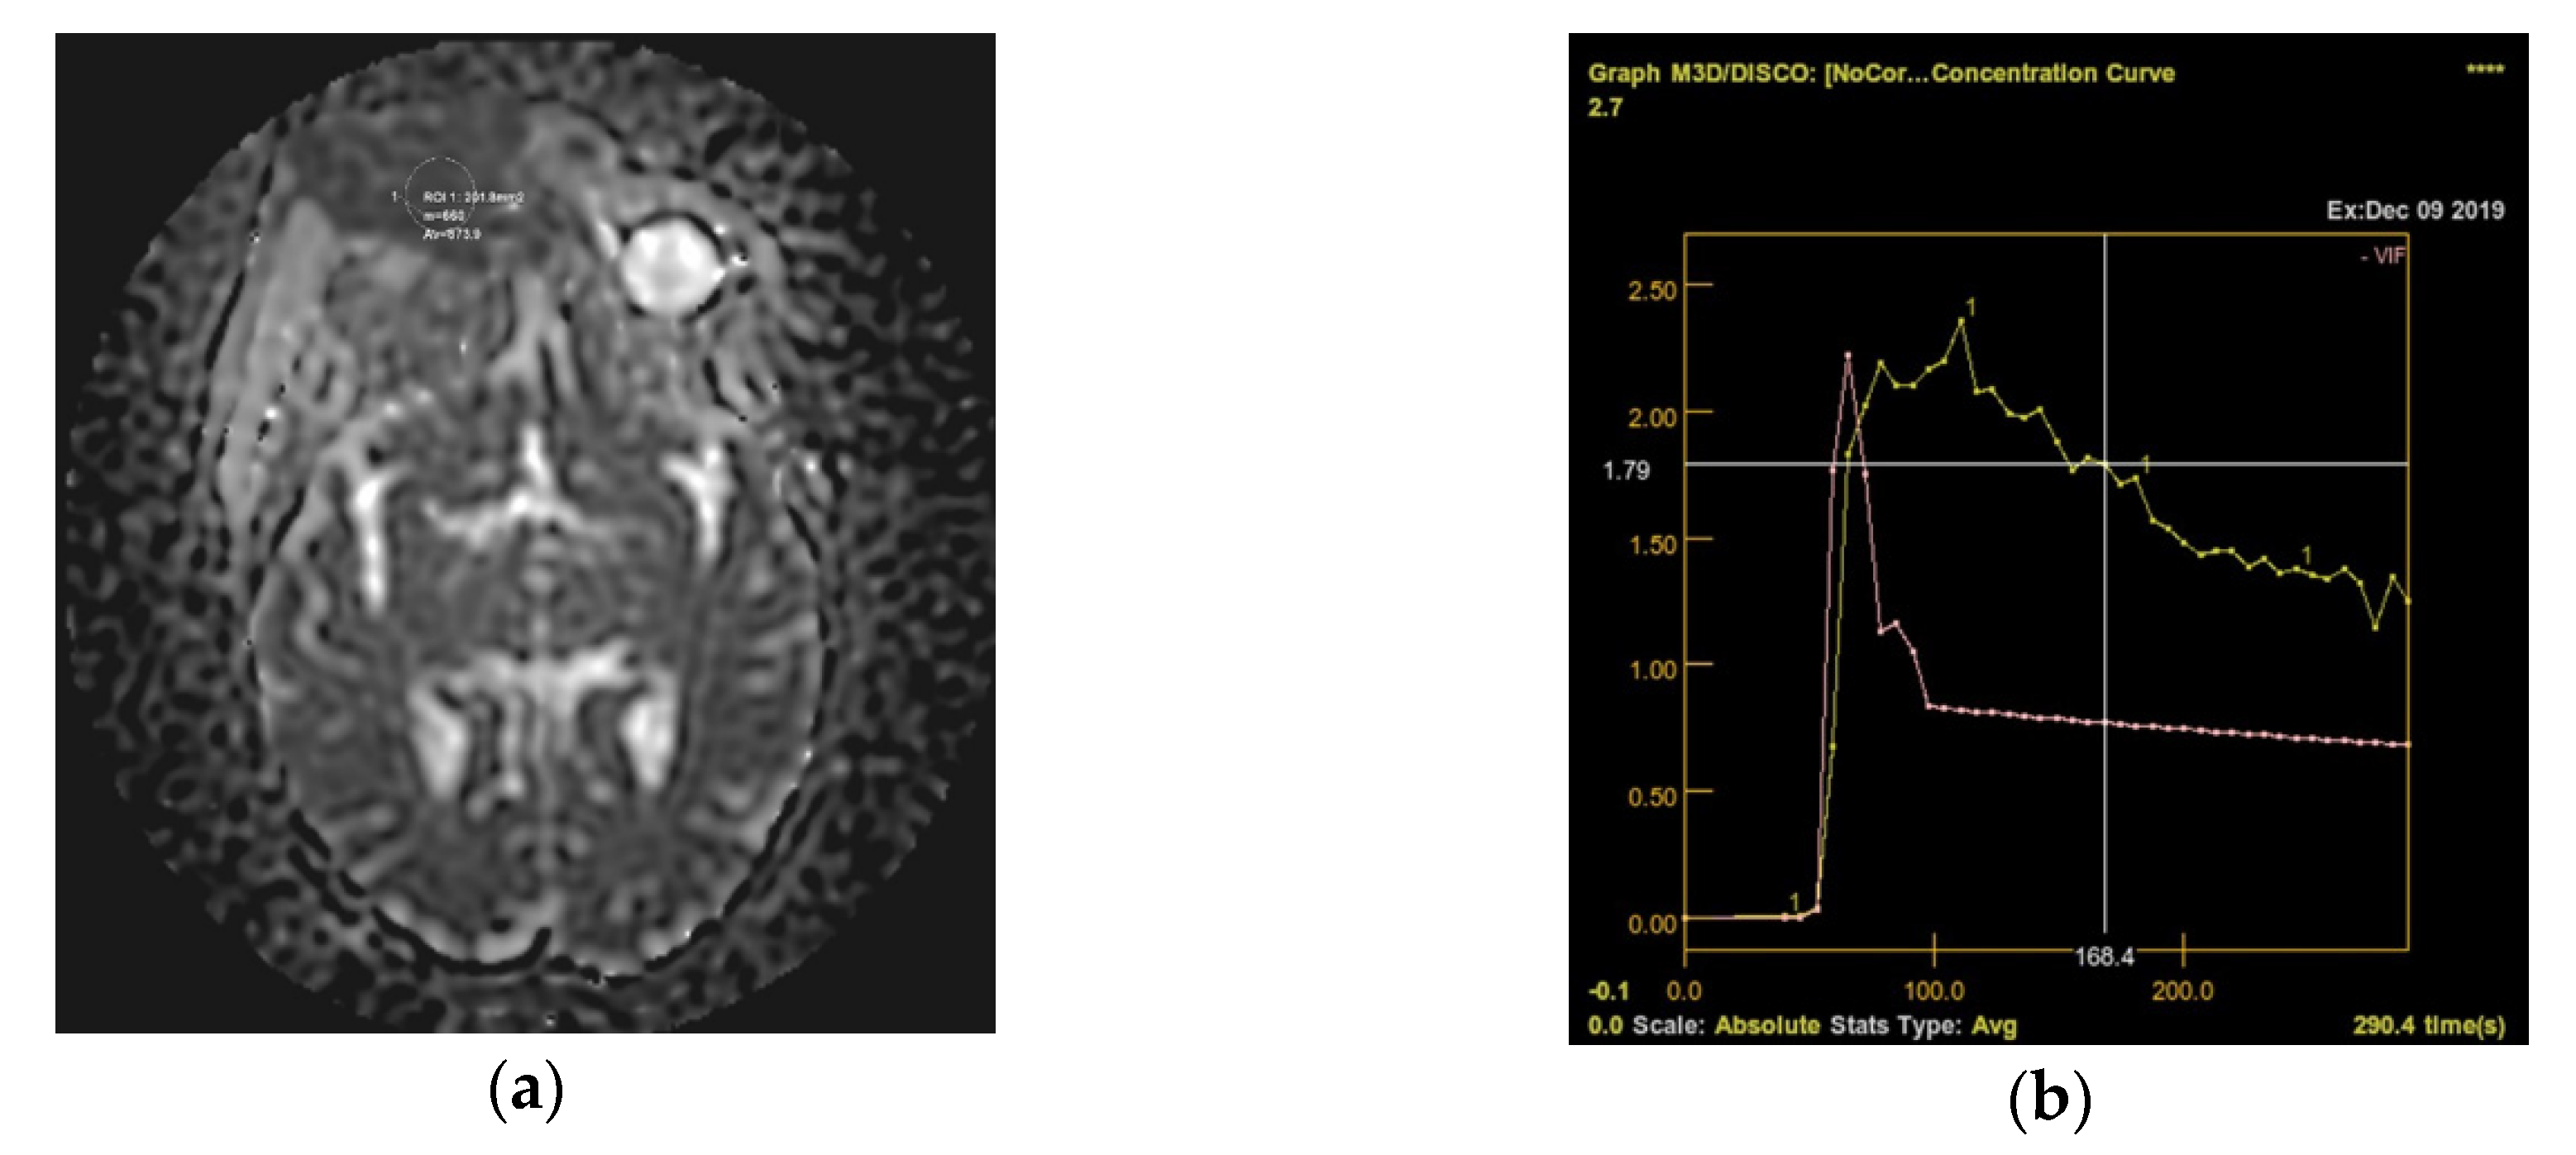

Following the immunohistochemical study, we obtained the following conclusive results. The tumor cells were intensely positive for CD3 (Figure 3b) and CD7 (Figure 3g), a relatively large number of tumor cells were positive for CD2 (Figure 3d) and CD4 (Figure 3e), and only a small population of T lymphocytes or some atypical larger cells were positive for CD8 (Figure 3f), with a CD4+/CD8+ ratio favoring CD4+ cells. Tumor cells were negative for CD30 (Figure 3i), CD5 (Figure 3c), and CD 56 (Figure 3h). A small population of atypical lymphocytes were positive in granzyme B after immunohistochemical staining. The cell proliferation index quantified by immunolabeling for Ki-67 was estimated and quantified at 80–85% (Figure 3j). Following the morphological examination correlated with special stains, the diagnosis of primary cutaneous T-cell lymphoma NOS was established. Whole-body CT was performed and revealed tumor formation in the soft epicranial parts, right frontal area, and supraorbital area, with dimensions of 22/50/45 mm. The lesion affected the upper eyelid and the paranasal region, with no signs of ocular or intracranial invasion. In the frontal on the median and parasagital line on the left, epicranial area, adjacent to the described lesion, another structure with 35/15 mm contrast socket was highlighted. The dynamic contrast-enhanced magnetic resonance imaging (MRI) revealed a large, inhomogeneous lesion, with infiltrative, invasive contour. The origin of the tumor was most probably from the periorbital superficial tissues, with invasion in the orbit and direct contact to the anteromedial aspect of the ocular globe without the presence of a cleavage plane between the two structures (Figure 4a,b and Figure 5a,b). Figure 4a shows that the T1 FSE (fast spin echo) axis and sagittal T1 FSE contrast-enhanced with fat-saturation sequence was not enhanced (a), whereas Figure 4b shows inhomogeneous enhancement of the lesion, with superficial tissue origin and invasion in the right orbit. Figure 5a,b depict the axis T2 PROPELLER sequence showing the necrotic areas in the primary and secondary lesion, satellite lesion in the superficial tissues of the frontal region (marked by arrows in the picture). A restricted diffusion on diffusion weighted imaging (DWI) sequences was observed, with an apparent diffusion coefficient (ADC) value of 0.873 × 10−3 mm2/s on the ADC map (Figure 6a). Dynamic contrast-enhanced MRI (DCE-MRI) imaging showed a type III (C) curve highly suggestive for malignancy (Figure 6b), and a high constant transfer (ktrans) value was observed, pointing to a possible good response to radiochemotherapy (Figure 7). In the proximity of the left frontal area, two nodular superficial lesions were identified, suspected of secondary nodules.

Figure 6. (a) Restricted diffusion on DWI sequences was observed, with an ADC value of 0.873 × 10−3 mm2/s on the ADC map; (b) Dynamic contrast-enhanced MRI (DCE-MRI) imaging showed a type III (C) curve highly suggestive for malignancy.